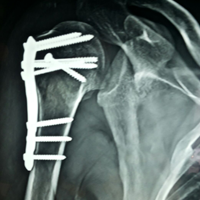

Case:17 Bilateral Fracture Dislocation

Known case of Epilepsy in 45-year-old Mason treated with open reduction & internal fixation with philos plate & locking screws bilaterally.

Right side Pre-Op

Right side Post-Op